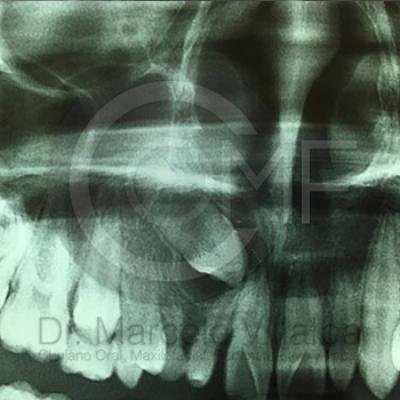

Canino Retenido2